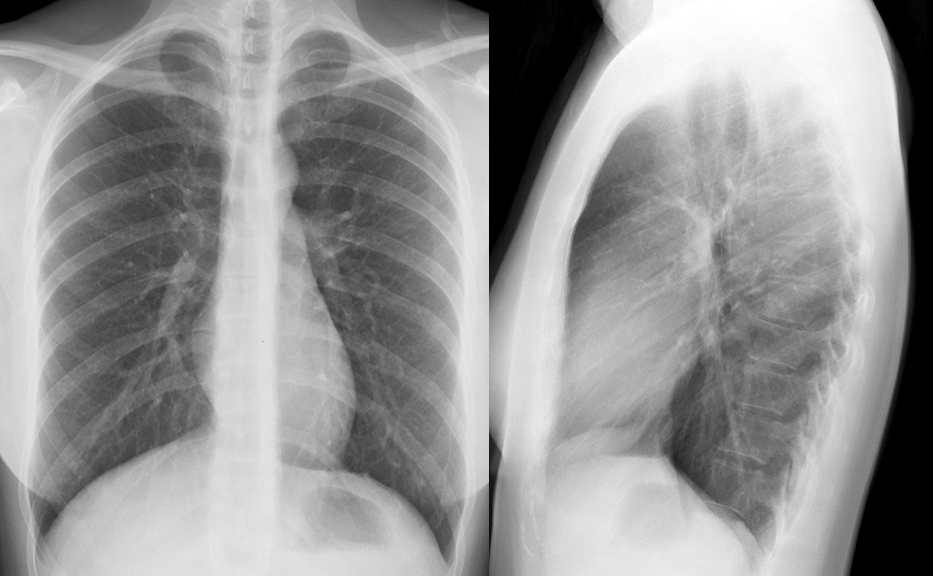

Gallery Normal and Variants Nl PA & Lat

Nl PA & Lat